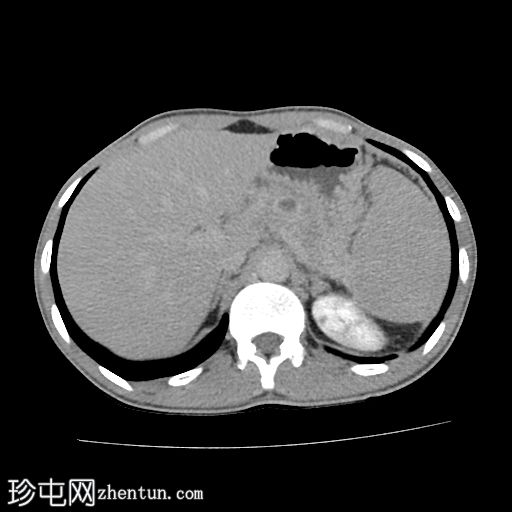

轴位

平扫

胰腺肿大。胰头、胰颈和胰体未见强化,边界不清且不规则。主胰管扩张,管内可见钙化。

胰腺实质内弥漫散在分布着大量钙化灶。

胰尾可见部分强化区域。

胰尾部钙化性假性囊肿。

影像学表现提示慢性钙化性胰腺炎伴胰尾部钙化性假性囊肿。